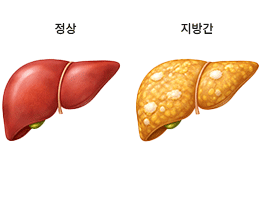

지방간 (Fatty Liver Disease)